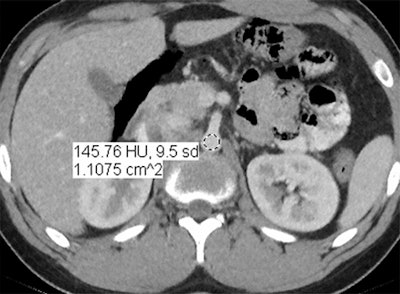

"We went back and looked at ... how the image quality was; whether we were able to see all the lesions we wanted to see; subjectively, how did the images look; and we looked at a couple of objective measures: image noise and the standard deviation of the Hounsfield units of a given region of interest," Smith said. "Our physicist used the exact same scanning parameters and actually scanned a phantom and looked at the spatial resolution -- and the phantom [image] was superior to standard dose using the MBIR technique."

Images are of a 17-year-old boy with a history of Hodgkin's disease. Reduced-dose MBIR image (above), reduced-dose 100% ASIR image (below), reduced-dose filtered back projection image (third from top), and comparison standard-dose 30% ASIR image (bottom), all with a region of interest in the abdominal aorta for objective noise measurement. The reduced-dose MBIR image has significantly less noise compared with other reduced-dose and standard-dose reconstructions. Images republished with permission of RSNA from 10.1148/radiol.13130362, October 3, 2013.

In an objective evaluation, reduced-dose MBIR images had decreased image noise compared with standard-dose 30% ASIR images (for example, 12.7 HU versus 19.4 HU in the aorta, respectively, and 8.7 HU versus 14.2 HU in the liver).